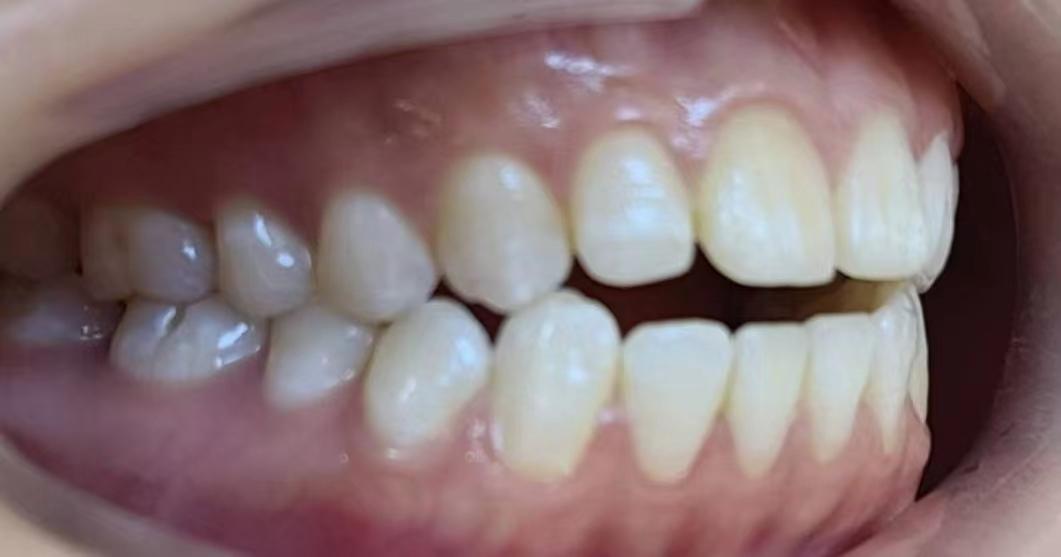

嘴凸不說下巴還后縮

沒有美美的側(cè)顏殺怎么拿下心動(dòng)男孩呢!!

咱不提倡整容!但咱天生的下巴要給他使喚出來吧!所以很多妹紙沒有下巴有可能不是天生的呢!